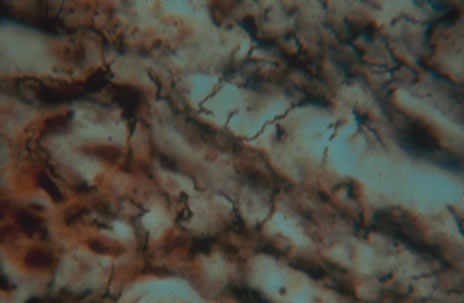

The acute retinal necrosis (ARN) syndrome is most often caused by the herpes zoster virus, although occasionally it may be a result of herpes simplex infection.12 It is typically described in healthy patients although association with immunosuppressed patients has also been described. Granular, nonhemorrhagic areas of retinal necrosis may be observed in the fundus, often rapidly coalescing with resulting blindness often caused by retinal detachment. There is often an associated vasculitis and vitritis. In immunocompromised patients VZV or HSV retinitis may also take the pattern of progressive outer retinal necrosis (PORN) (Fig. 6). PORN differs from ARN in that the former is multifocal, localized to the outer retina, and is less often associated with vasculitis and vitritis.

Any cell type may be infected, appearing larger than normal (cytomegalic) and demonstrating eosinophilic intranuclear “owl's eye” and smaller intracytoplasmic viral inclusion bodies, which are better seen with Giemsa or Papanicolaou's stains (Fig. 8). Histologic examination of tissue specimens, including bronchoalveolar lavage fluid and urine, may be useful for diagnosis.